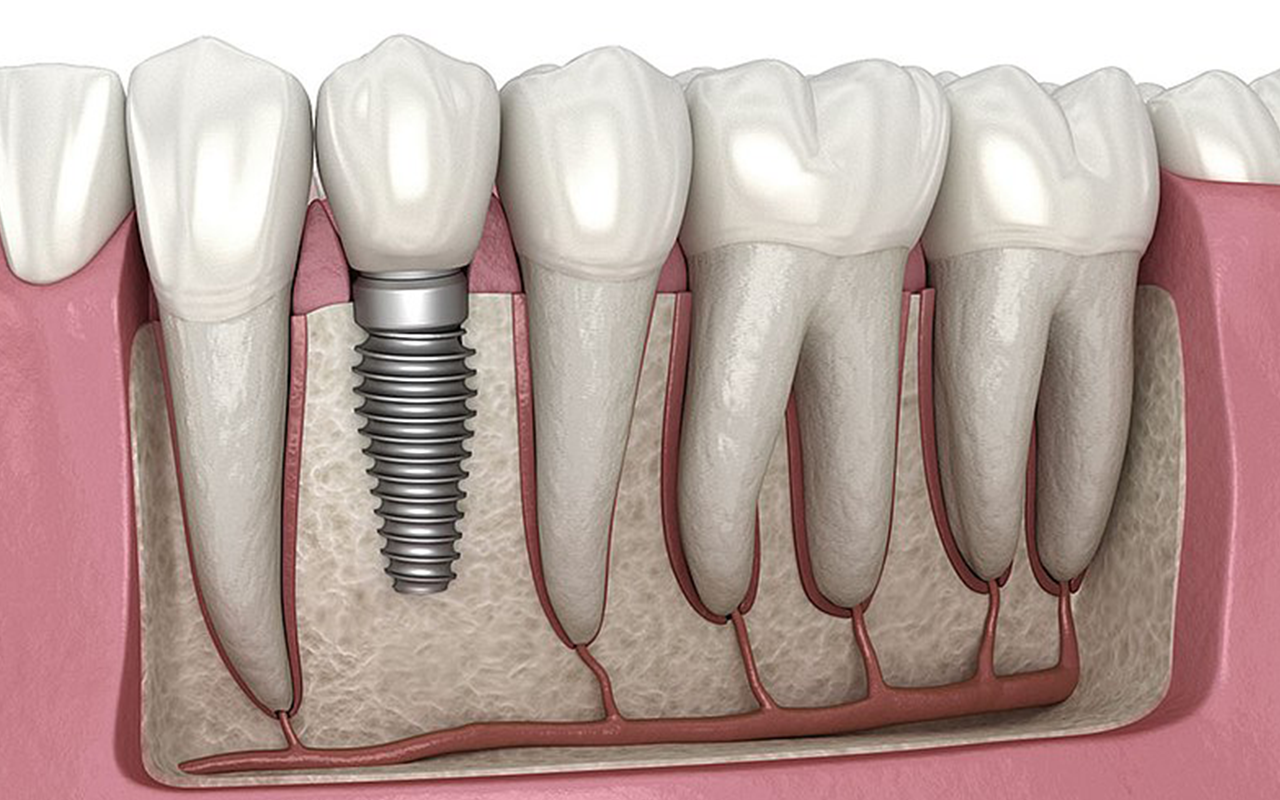

Planlama aşamasından sonra, implantlar cerrahi bir işlemle çene kemiğine yerleştirilir. Lokal anestezi altında yapılan bu işlem genellikle ağrısızdır.

Cerrahi işlemden sonra, implantların kemikle kaynaşması için 3-6 ay arasında bir iyileşme süreci gerekir. Bu süre boyunca, geçici protezlerle estetik ve fonksiyonel açıdan destek alabilirsiniz.

İmplantlar kemikle kaynaştıktan sonra, üzerlerine protezler yerleştirilir. Bu protezler, tek diş eksikliğinde tek kron, birden fazla diş eksikliğinde köprü veya tam protez şeklinde olabilir.